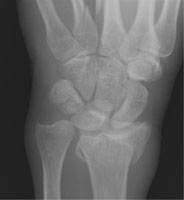

- Click on the image for a larger versionCPA radiograph of the wrist. This demonstrates an impacted fracture of the radius.